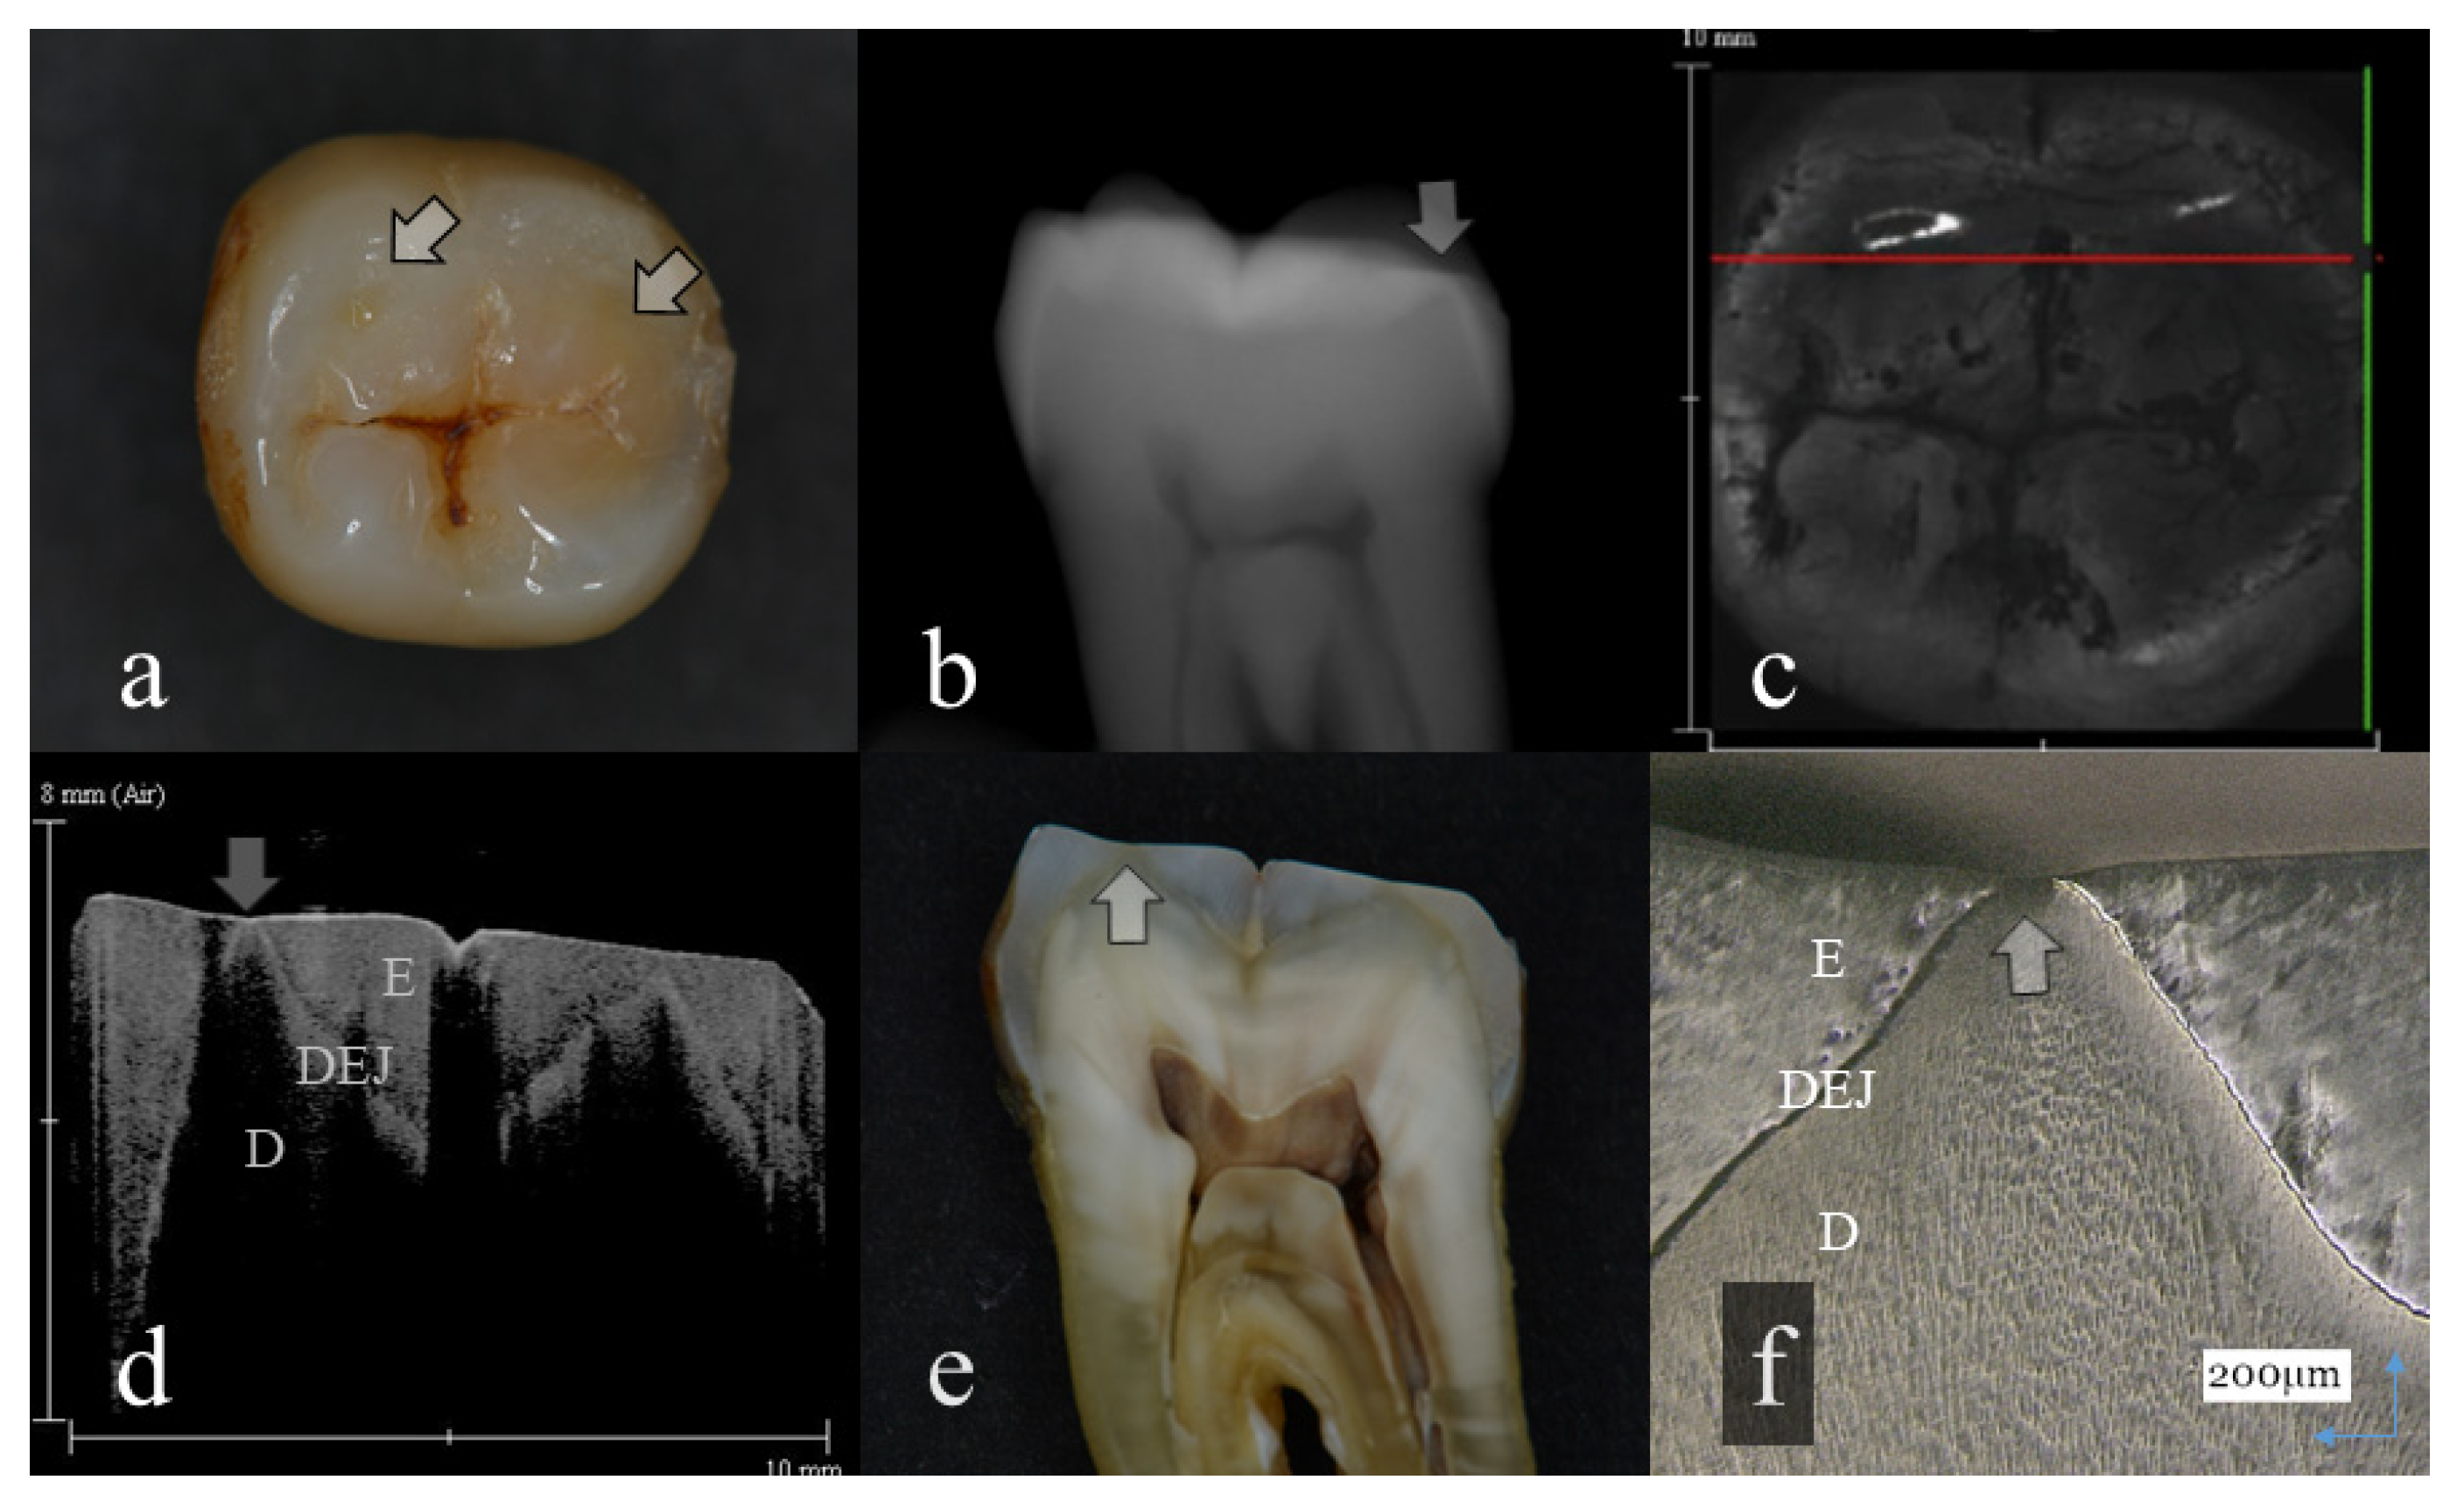

Figure 1.

Slight enamel wear (score 1): (a): Occlusal view. Visibly, evidence of occlusal tooth wear was not observed; (b): Digital intraoral radiography; (c): Optical coherence tomography (OCT) en face intensity projection; (d): Swept-source (SS)-OCT image. Occlusal enamel and underlining dentin were distinguished by the dentin enamel junction (DEJ) (arrow); (e): Histological view; (f): Confocal laser scanning microscopy (CLSM) image of histological view. A tip of the cusp was slightly cracked (arrow). However, the anatomical shape of the cusp was maintained. The corresponding dynamic slicing 3D video is in Supplementary Materials: Video S1. The upper right is a cross-sectional image. Lower right is an en face image.

In OCT, amount of enamel loss could be estimated by the cross-sectional view of remaining enamel thickness, as the DEJ was clearly visualized as a landmark in all the OCT scans (Figure 1 and Figure 2). Since intact enamel allows the OCT signal to penetrate deep with less scattering, the whole thickness of occlusal enamel could be monitored in this study, resulting in the higher agreement with histological findings (Table 3). These results correlate well with previous study findings measuring the remaining enamel thickness of tooth wear surfaces using cross-polarization (CP) OCT [25,26]. The CP-OCT measurement of remaining enamel thickness was reported to show excellent agreement with the μ-CT measurement [25,26]. Meanwhile, as the enamel thickness is highly location dependent, 3D OCT could visualize the remaining enamel thickness for the area of scanned tooth surface to find the position with the remaining enamel becoming thinner, without the need for additional scanning (Videos S1 and S2). Consequently, dentists allow finding of the location where therapeutic management is necessary, even for patients at the asymptomatic stage. In radiography, level of enamel wear is difficult to see because of the superimposition of dense buccal and lingual cusps, and visual inspection from the occlusal view estimating the topographical and color changes appears more informative in many cases.